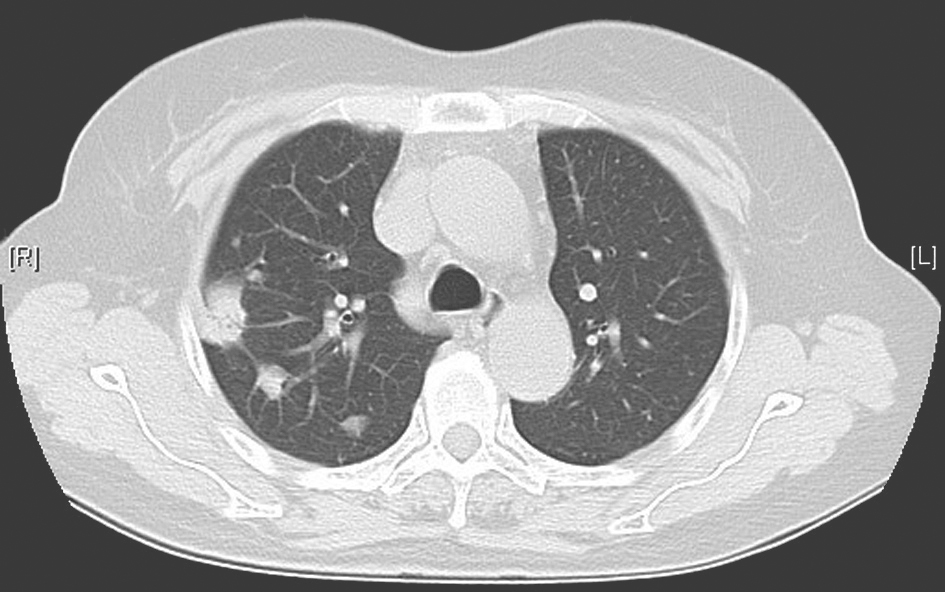

如肺结核、肺真菌感染(曲霉菌、隐球菌、组织胞浆菌等感染)。①肺结核患者多有午后低热、盗汗、咯血、食欲减退等结核中毒症状,病灶常位于肺上叶尖后段及下叶背段,而双肺多发结节病灶常见于血行播散型肺结核及支气管播散型肺结核。血行播散型肺结核影像学表现为双肺弥漫性粟粒样结节,支气管播散型肺结核则表现为小叶中心性结节,即树芽征改变;②肺曲霉菌感染患者多有免疫力低下等危险因素或肺部原有空洞继发感染,影像学表现为结节周围有晕征或空气新月征(图3);③肺隐球菌病常见于社区感染,多表现为咳嗽、咳痰、咯血、胸闷、胸痛、低热等,影像学表现可见孤立性结节或双肺多发结节(图4),多于近胸膜下分布,有时结节周边也出现晕征。

图4 肺隐球菌病胸部影像学表现

胸部CT可见右上肺多发结节性高密度影